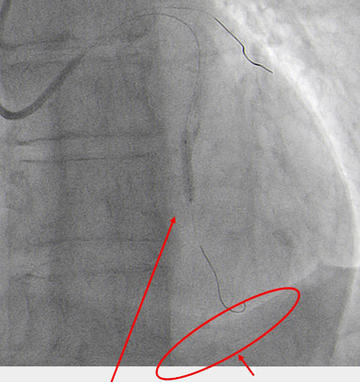

NC 2.5 x 30 mm balloon predilatation and 2 DES implantation in overlapping (Figure 6.1).

Predilatation with NC balloon (Figure 6.1)

After overlapping post-dilatation, Type III coronary perforation and sudden cardiac tamponade occurred (Figure 6.2).

Type III perforation and cardiac tamponade (Figure 6.2)

Stop coronary flow as soon as possible with balloon inflation technique. Implementation of pericardiocentesis, no Protamine (Figure 7.1).

Quick pericardiocentesis with 6F femoral sheat and balloon dilatation to stop coronary flow (Figure 7.1)